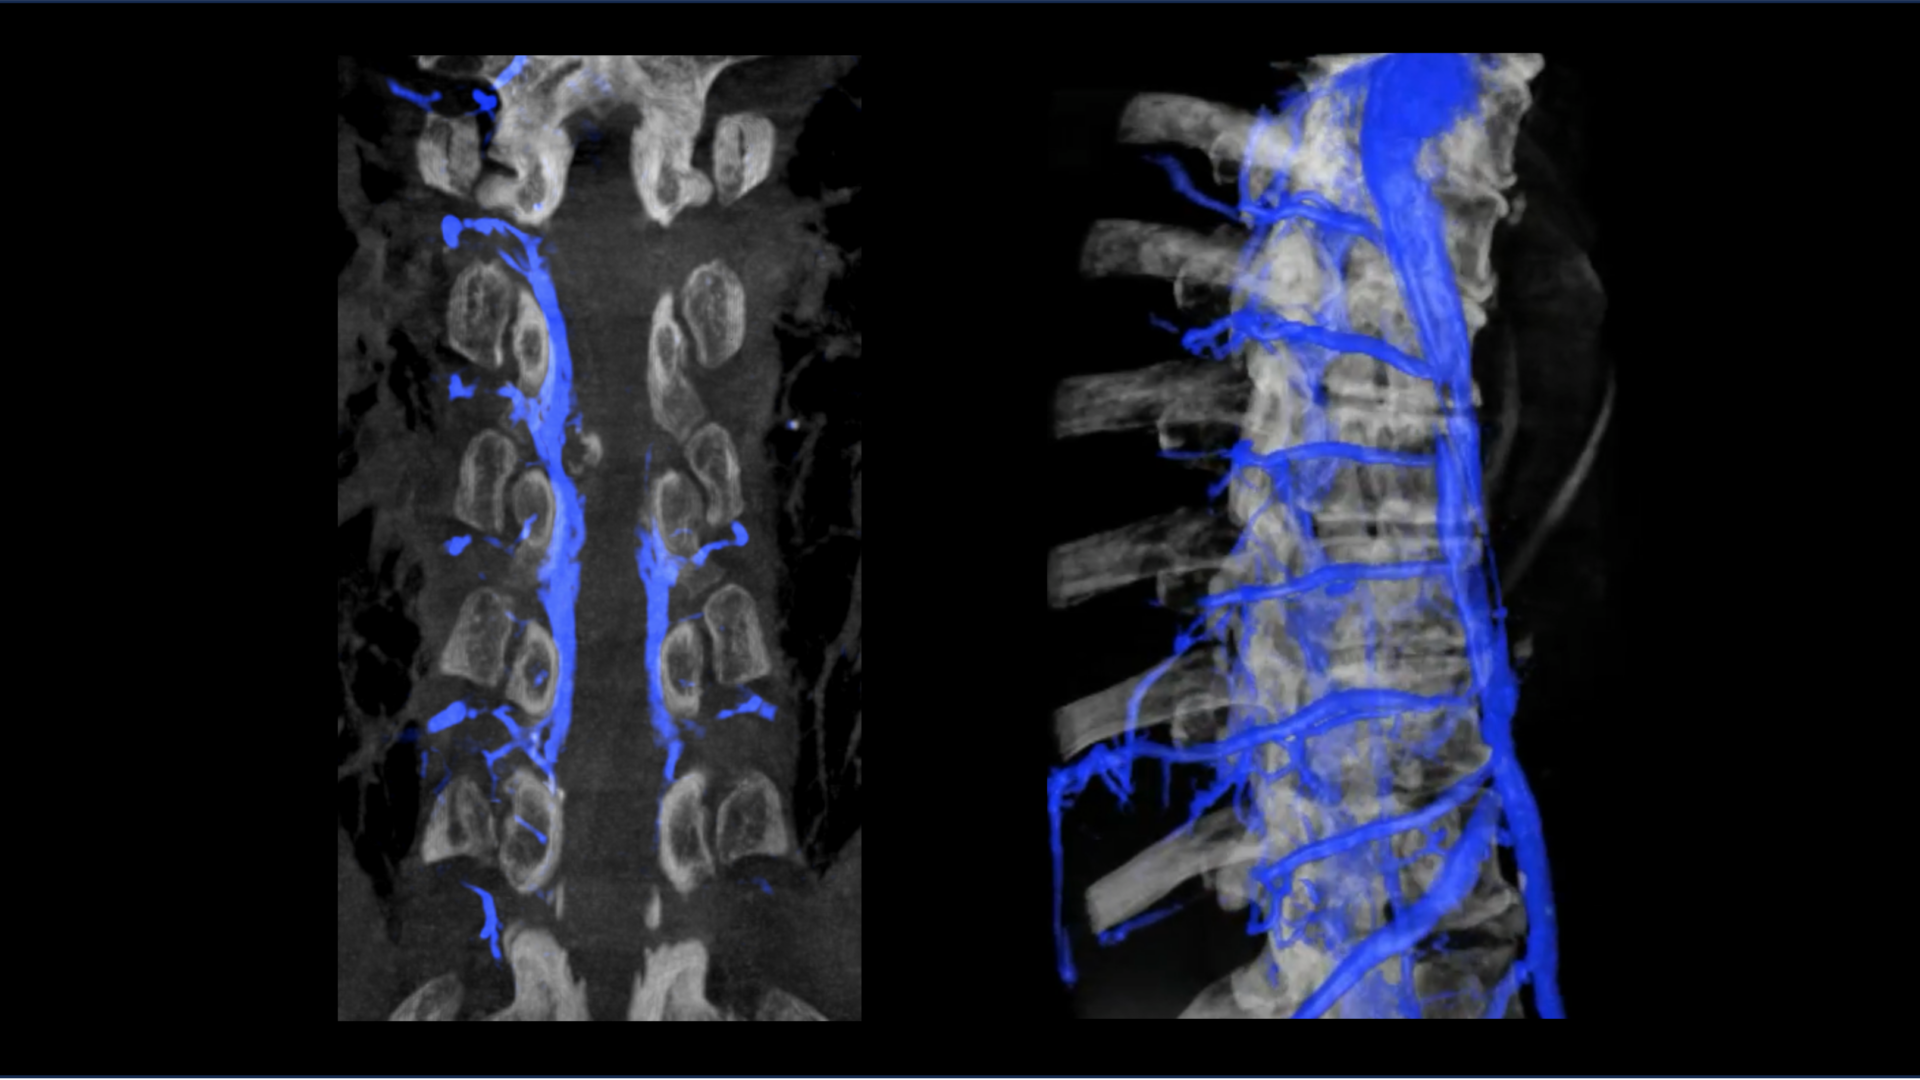

The abnormal connection occurs between the spinal subarachnoid space and a nearby spinal vein, permitting CSF to flow directly into the venous system. The fistulas typically occur in the thoracic spine and sometimes in the lumbar region. The cause is unknown and they’re seen across all clinical contexts—affecting the young and old, male and female, healthy and sick alike.

Instead, a brain MRI may detect changes indicative of CSF volume depletion, including meningeal enhancement and “brain sag,” or the downward displacement of the brain within the skull. Dynamic myelographic techniques are relied on to confirm the abnormal flow of CSF into a vein and pinpoint the leak’s location.

At NYU Langone, lateral decubitus CT myelography is the specific imaging recommended when a CSF–venous fistula is suspected. To increase chances of detecting the leak, multiple CT acquisitions are performed, including immediately after the dye is injected and at later timepoints, and with the patient rotating between lying on their right and left sides.

The general approach to the embolization is to gain access via the femoral vein and advance a catheter into the target paraspinal vein identified as draining the fistula. Roughly 1 to 2 mL of an embolic agent is slowly released. Fluoroscopic imaging is used to confirm that the embolic agent successfully occludes the pathway for CSF leak.